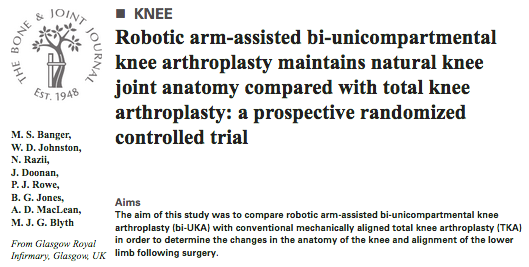

Robotic arm-assisted bi-UKA has a similar safety profile to traditional mechanically-aligned TKA surgery over the first postoperative year ow.ly/EFvk50Gmtim #Arthroplasty #Robotics Ortho-GRI Matthew Banger James Doonan

TRUCK RCT: Biomechanical function outcomes published in the Bone & Joint Journal online.boneandjoint.org.uk/doi/full/10.13… James Doonan Ortho-GRI Biomed Engineering